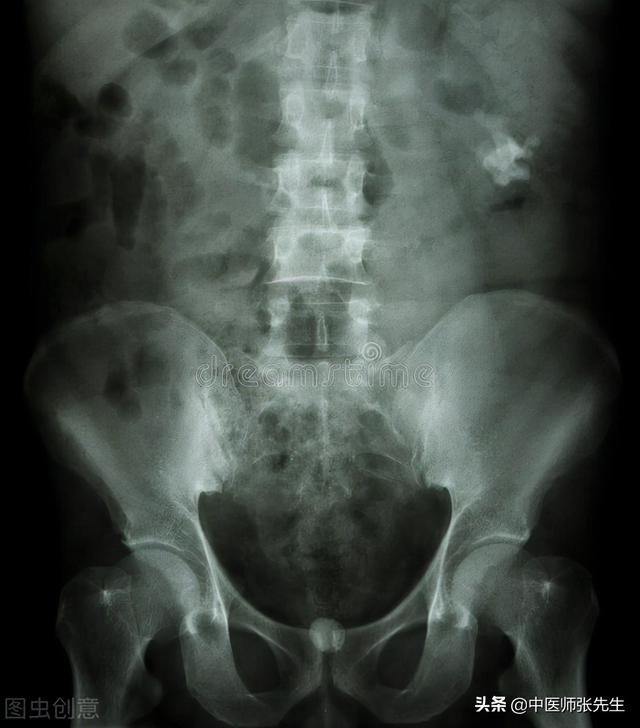

鸡内金可治胆结石

杀鸡时,在鸡的嗉囊里面,会发现很多小石头,这些小石头,在鸡的胃里面反复碾磨,有助于食物的消化,但鸡的嗉囊内壁,却不会因为这些石头的碾磨而受伤。古人通过这些观察,从而推断出鸡嗉囊内壁(也就是鸡内金),具有消化饮食和消磨石头的作用,配伍其他药物一起使用,能治疗胆结石、肾结石。

对于肝内胆管结石患者来说,如果已经很长时间,经过观察结石没有变化,临床也没有症状,那可能不需要治疗。继续观察定期复查就是。如果想吃中药,需要辨证论治才好处方,不然,方不对症就难以取得效果。

当然通过中医调养治疗也是可以完全痊愈。中医认为,肝内胆管结石属“胁痛”、“黄疸”范畴。肝主疏泄,具有疏泄、贮藏、调节等作用,性喜条达,所以情志失调或暴怒伤肝,使肝失条达,疏泄不利,或气郁致血流不畅,气滞血瘀,或脾失健运,痰湿中阻,或肝肾阴虚,均可导致肝内胆管结石的发生。

治疗身体结石的两味妙药

临床常见的症状就是两胁胀痛,牵引右肩背不适,口苦咽干,心烦,或低热腹胀,舌苔薄黄,脉弦等,或无任何症状。肝内胆管结石,虽然其病位在肝,但与脾、胃、肾密切相关,通过中医调养,实脾、补肝,肝旺则疏泄畅达,胆管收缩有力。健运脾、胃,消积溶石、化石,荡涤积滞,因势利导,兼顾脾胃,调扶正气,攻补兼施,刚柔相济,正气充沛,使胆汁排泄通畅无阻、结石得以溶解、消散,肝脏功能恢复正常。肝内胆管结石的患者可以通过中医调养治疗,以药疗为主,以食疗、手法治疗为辅,大概两个疗程即可痊愈。